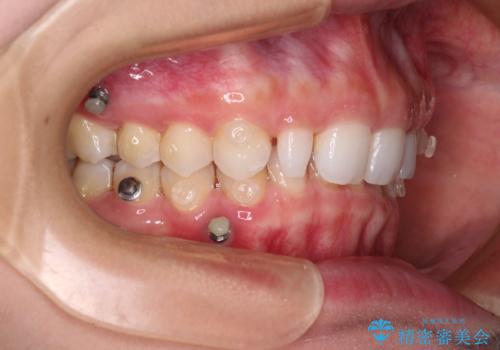

アンカースクリューを用いて上顎歯列全体を後方移動させ、極力過蓋咬合も改善されるよう計画しました。

インビザラインは長時間装着を自己管理する必要がありますが、残念ながら十分な時間の装着を行うことができませんでした。

何とか矮小歯を改善するスペースを作ることはできましたが、過蓋咬合を改善するには至りませんでした。